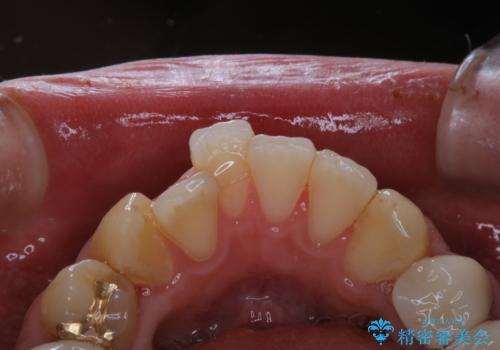

前歯の着色をPMTCできれいに